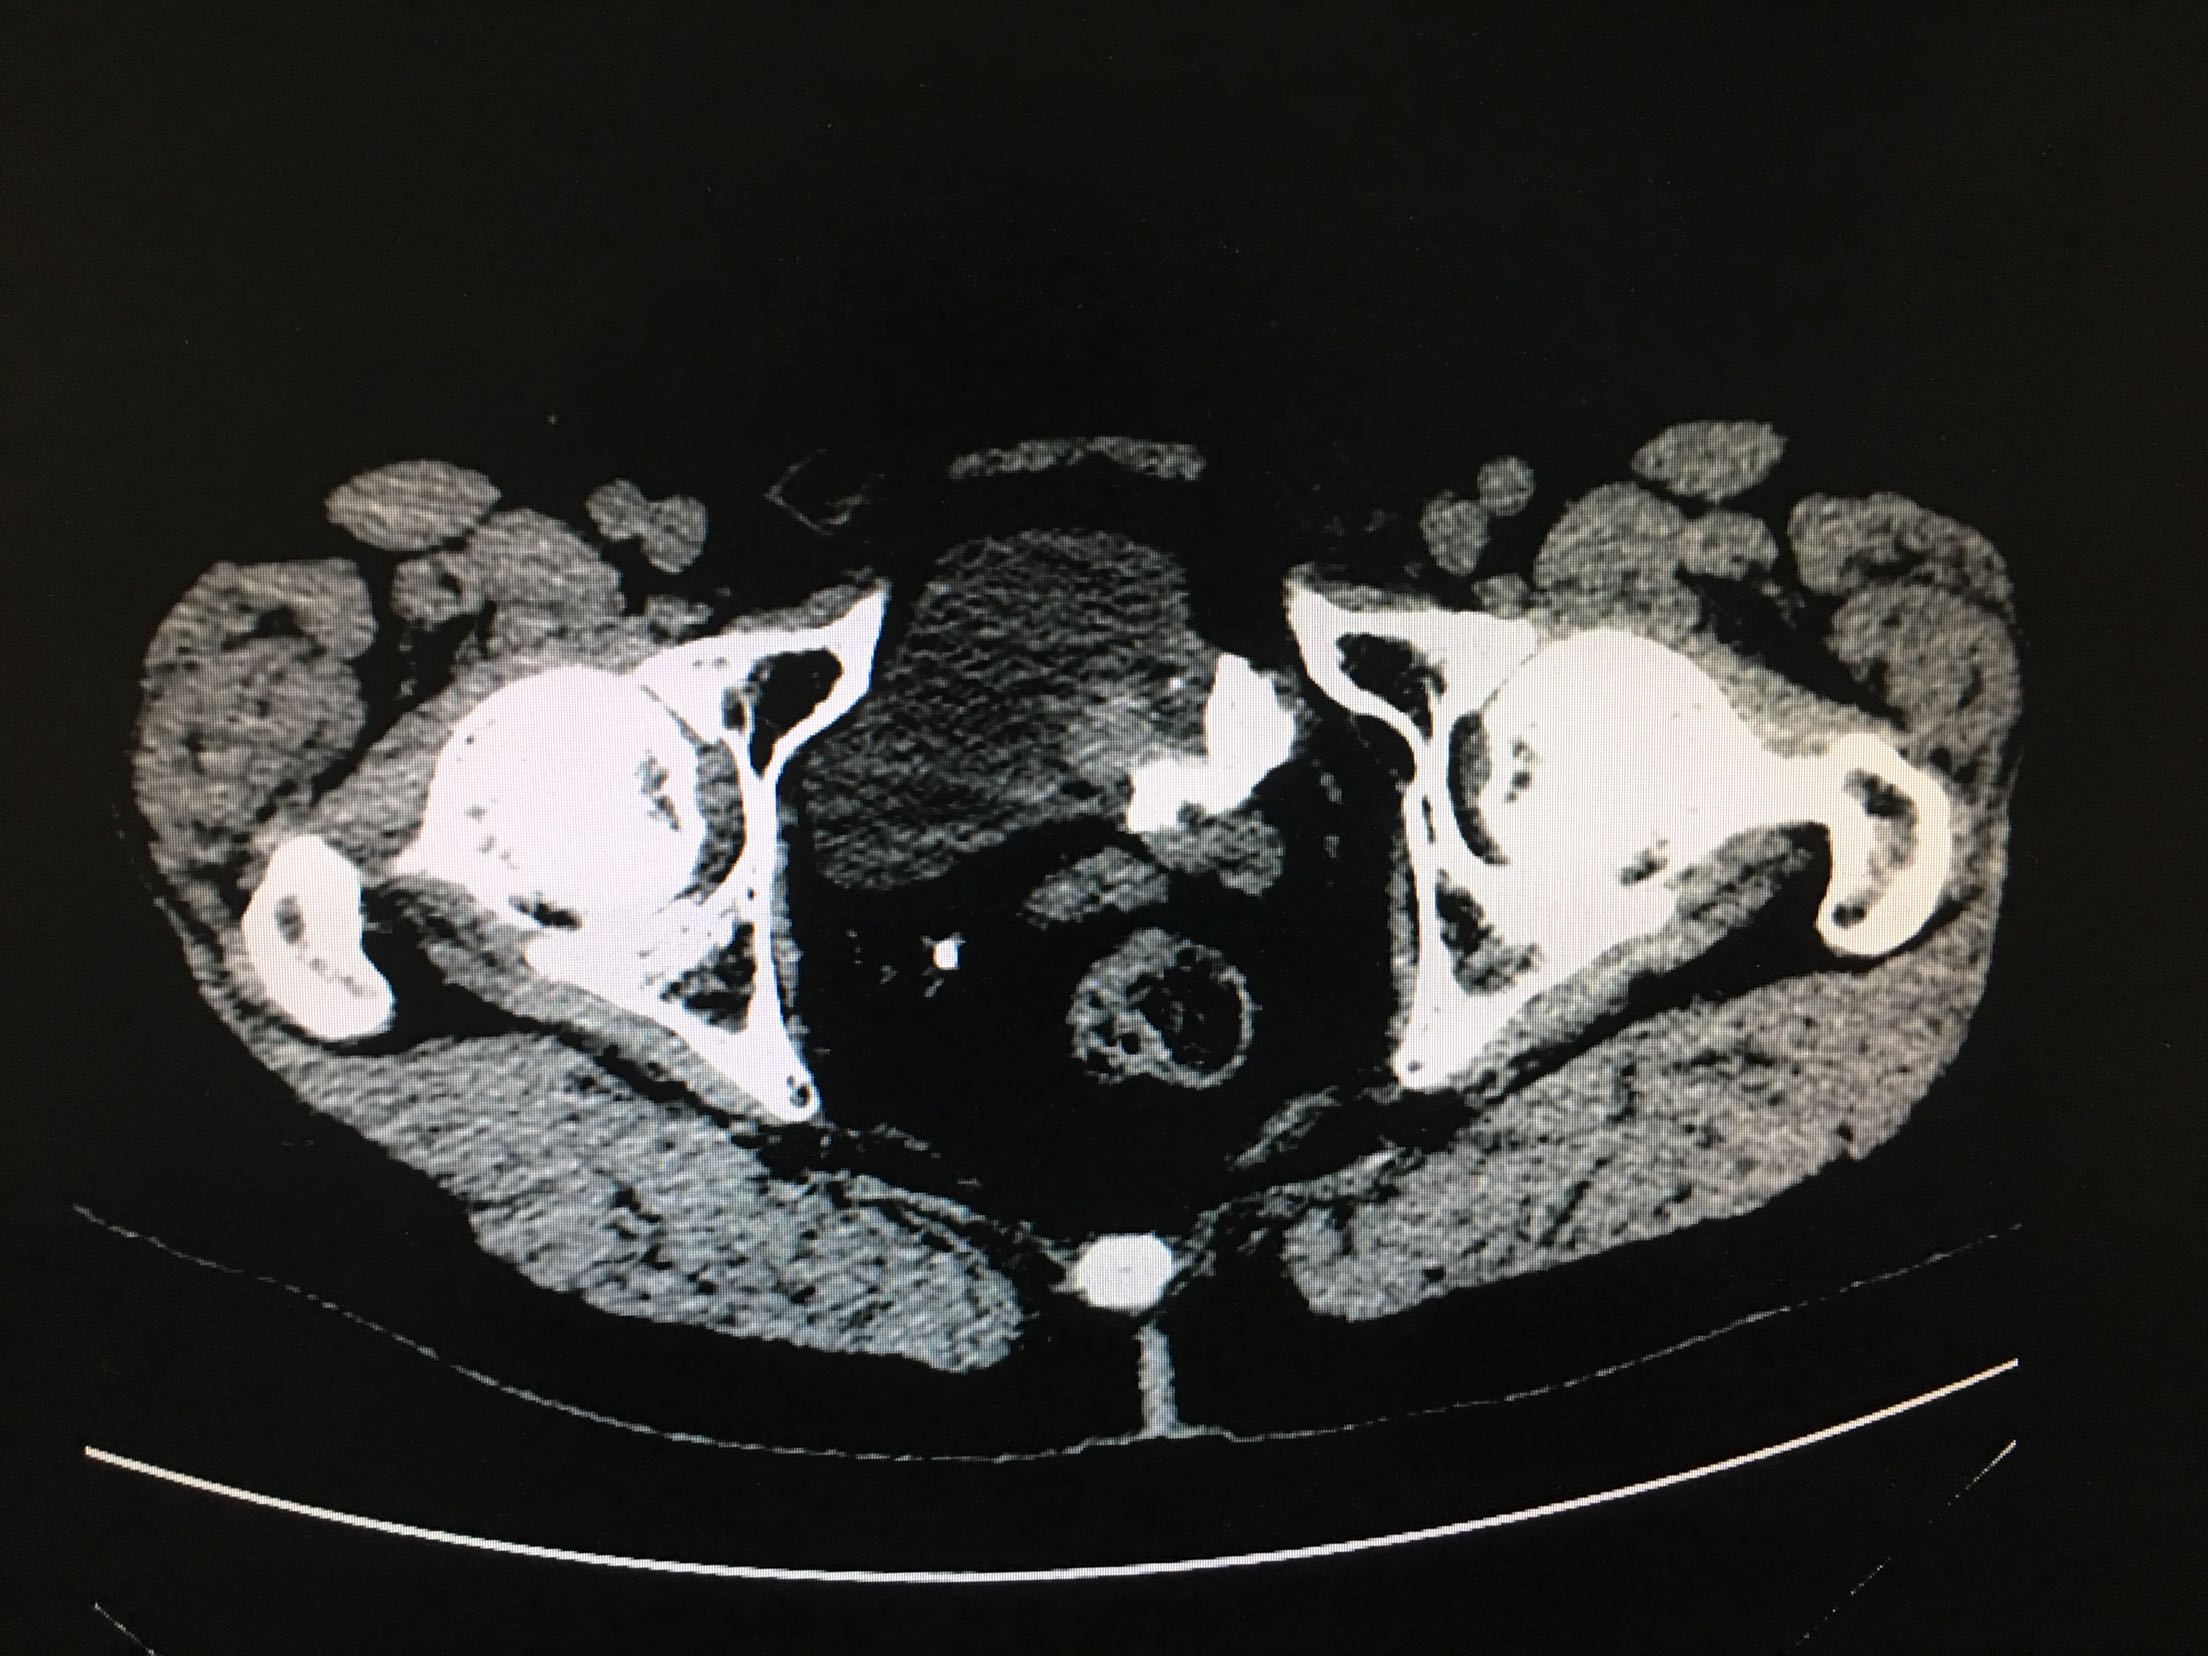

67岁男患者 2年前患者因为尿潴留检查发现前列腺癌,行经尿道前列腺癌电切改善排尿,术后给予内分泌治疗,5天前患者出现肉眼血尿,尿频、尿急、尿痛症状严重。患者为求进一步诊治来我院。患者发病以来精神状态差,体重减轻。

查体:双肾区无叩击痛,双输尿管走形区无压痛,耻骨上压痛,叩诊未见明确浊音。 辅助检查:ctu:膀胱占位性病变及直肠壁增厚,结合病史考虑前列腺癌伴膀胱及直肠受累。 psa:35ng/ml。